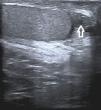

En la ecografía escrotal se observó un nódulo quístico de 13×12mm, isoecoico al testículo y con zonas hipoecoicas (fig. 2).